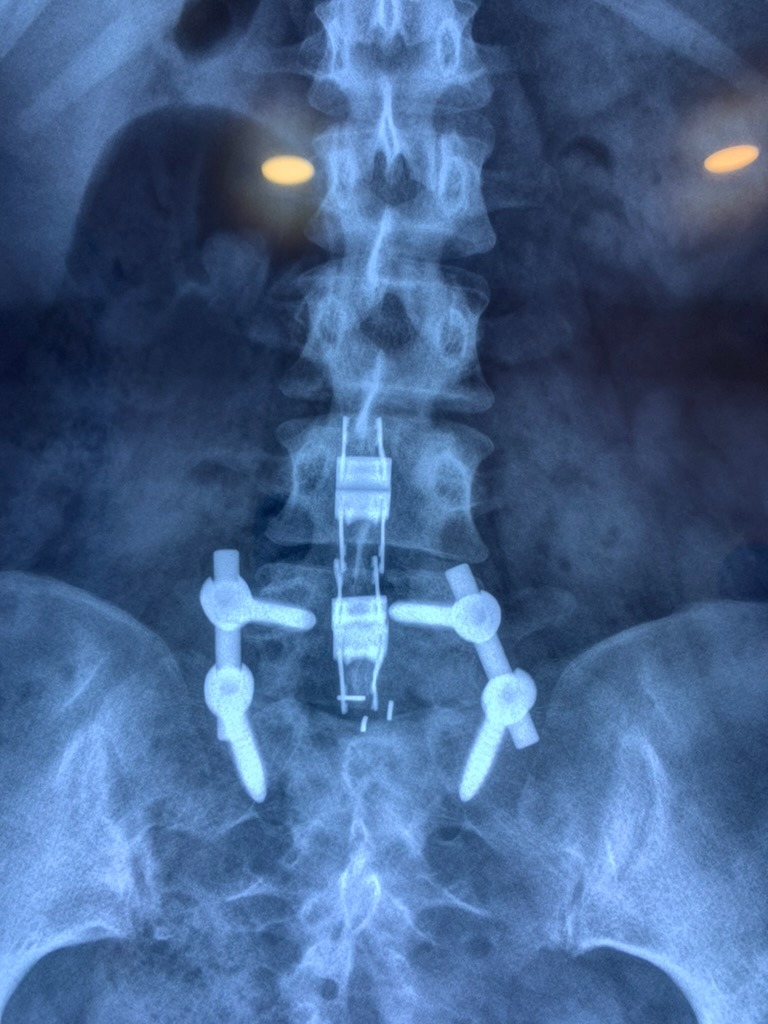

RESULTADOS